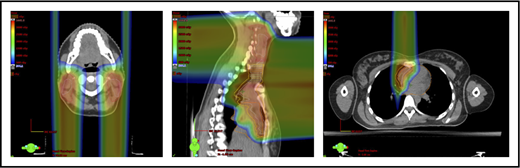

For the purposes of this article, proton and photon plans in all of the illustrations shown use DIBH, inclined board for females to further avoid the breasts and, for IMRT, a butterfly technique.48-51

Three scenarios of the relation between mediastinal disease and the heart. (A) Showing how to use the takeoff of the left main stem coronary artery (outlined in pink) to determine the upper and lower mediastinal locations. (B) Scenario 1: coronal CT images of a 28-year-old man with primary mediastinal lymphoma before (i) and after (ii) 6 cycles of rituximab, cyclophosphamide, doxorubicin, vincristine, prednisone (RCHOP) chemotherapy presenting for consolidation with radiation. (Biii) Axial, coronal, and sagittal views of an IMRT plan (upper panels) and a proton plan (lower panels). (Biv) Corresponding mean doses to critical structures using IMRT vs protons. (C) Scenario 2: coronal CT images of a 25-year-old man with Hodgkin lymphoma before (i) and after (ii) 4 cycles of doxorubicin, bleomycin, vinblastine, and dacarbazine (ABVD) chemotherapy presenting for consolidation with radiation. (Ciii) Axial, coronal, and sagittal views of an IMRT plan (upper panels) and a proton plan (lower panels). (Civ) Corresponding mean doses to critical structures using IMRT vs protons. (D) Scenario 3: coronal CT images of a 30-year-old man with recurrent Hodgkin lymphoma as shown in the coronal images of a PET/CT scan (i-ii) presenting for definitive radiation. (Diii) Axial, coronal, and sagittal views of an IMRT plan (upper panels) and a proton plan (lower panels). (Div) Corresponding mean doses to critical structures using IMRT vs protons.